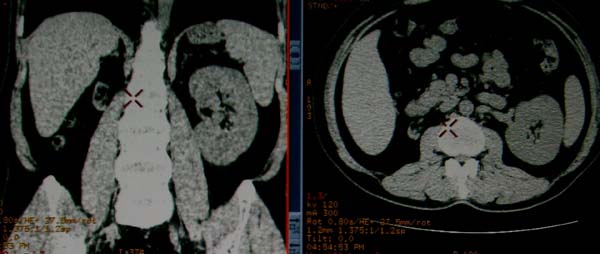

标题: CT17174:M38Y,体检超声提示右肾发育不良,病人无明显不适 [打印本页]

标题: CT17174:M38Y,体检超声提示右肾发育不良,病人无明显不适

右肾发育不良;考虑左肾下极血管平滑肌脂肪瘤可能,建议增强。

右肾微小发育不良  左肾下极错构可能

1)左肾下极占位性病变,不排除肾癌可能;建议行进一步检查。2)右肾发育不良。

左肾下极占位性病变,不排除肾癌可能;建议增强及明确内部组织ct值。右肾发育不良。

右肾发育不良。左肾下极占位。

右肾发育不良。左肾代偿。左肾下极占位,性质待定,建议强化。

右肾发育不良。左肾下极占位。建议增强!

右肾发育不良。左肾下极囊实性占位,建议增强。